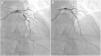

Due to intermediate risk findings on the treadmill test, coronary computed tomography angiography (CCTA) was requested for further assessment. The coronary calcium score was 105.2 Agatston units and an intermediate stenosis was identified in the proximal left anterior descending artery (LAD) due to non-calcified plaque (Figure 1A and D, arrow). Because the physiologic significance of the lesion was unclear, computed tomography-derived fractional flow reserve (CT-FFR) was determined using a workstation-based software prototype (cFFR, Siemens AG Healthcare, Forchheim, Germany). The value of CT-FFR just beyond the proximal LAD stenosis was 0.75 (Figure 2). The patient was referred for invasive coronary angiography (ICA) which confirmed a 75% stenosis in the proximal LAD (Figure 3B and Supplementary Video S1). Invasive FFR assessed in the LAD showed a similar result (0.76) to that observed on CCTA (Figures 3A and 3C). The patient successfully underwent percutaneous coronary intervention with a drug-eluting stent (Figure 4) and was asymptomatic after the procedure. This case illustrates the value of CT-FFR as a gatekeeper prior to ICA, to appropriately select patients and vessels for revascularization.

Correlation between invasive coronary angiography and coronary computed tomography (CT) angiography. (A) CT-derived fractional flow reserve (FFR) imaging showing an intermediate stenosis in the proximal left anterior descending artery (LAD) with a computed FFR of 0.75; (B) invasive coronary angiography confirming a 75% stenosis in the proximal LAD; (C) the measured value of invasive FFR was 0.76, which showed a good agreement with the CT-derived value (A).